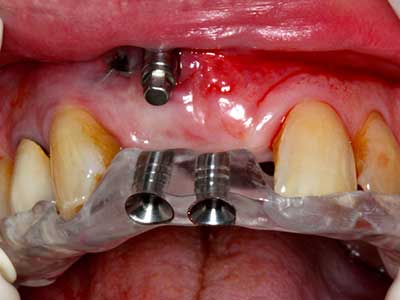

As shown in the past, basically any bone surgery procedure represents a possible indication for piezosurgery. Thus preparation of the mobile segment in distraction osteogenesis (Fig. 23-25) and sandwich osteotomy uses special attachments without endangering the blood supply to the crestal section, which is essential for the success of both techniques (Gonzalez-Garcia, Diniz-Freitas et al. 2008).

Fig. 21: Extended maxillary anterior-tooth defect with indication for distraction osteogenesis with scar tissue after prior operation.

Fig. 22: The mobile segment can be precisely separated with the thin osteotomy saw (W&H Piezomed).

Fig. 23: Final mobilization of the palatally branched distraction segment with the chisel.

Fig. 24: Application of the distractor (TRACK-System, KLS Martin).